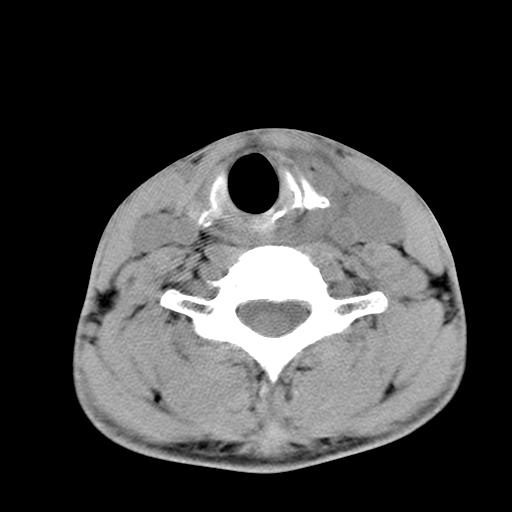

标题: CT15118:f-27y,左颈部肿一个月,无发热、无压痛 [打印本页]

标题: CT15118:f-27y,左颈部肿一个月,无发热、无压痛

1、甲状腺左叶病变:腺瘤?结节性增生?其他?

2、上极周围间隙病变。

3、2者关系?

左侧甲状腺肿大,密度不均.同侧甲状软骨似有破坏(建议传骨窗).左侧颈静脉增粗,各组织之间分界不清,有多个肿大淋巴结.甲状腺肿并感染?临床症状不符.淋巴结核?请结合其他检查.